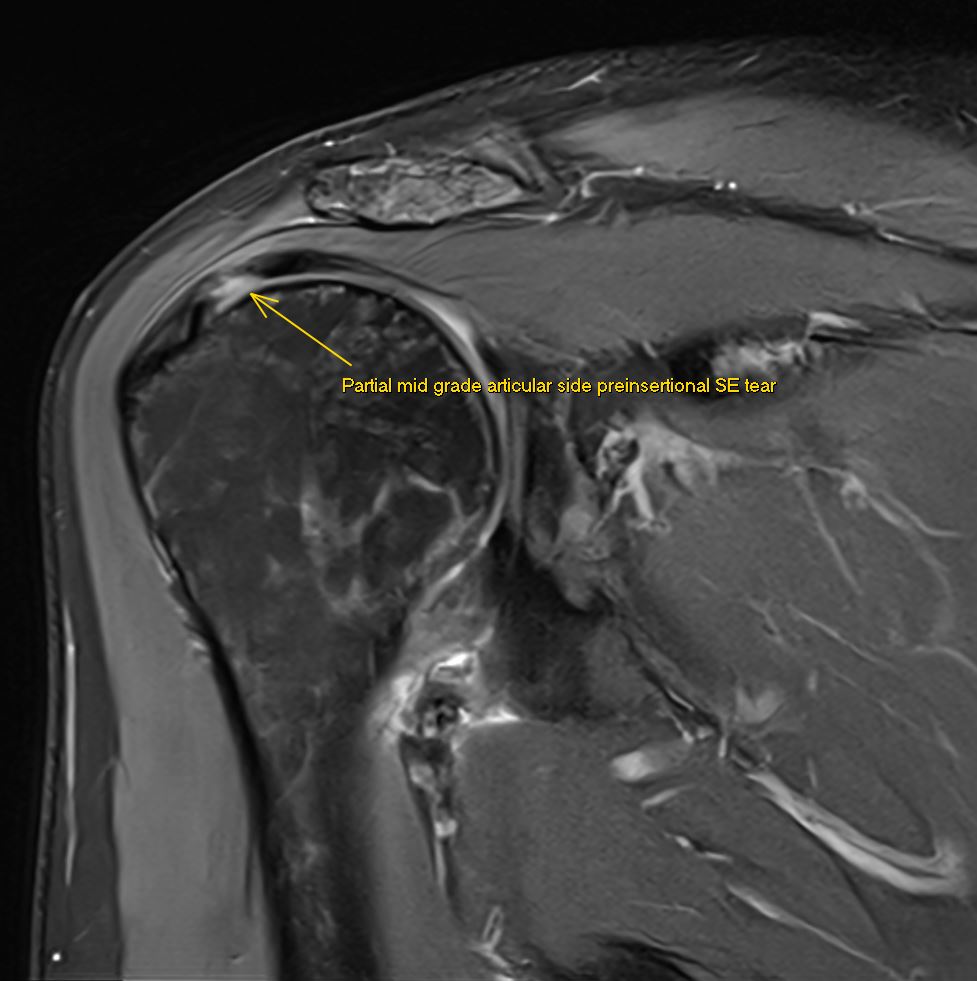

5/6/2024. 👌 Thrilled to have improved MRI protocols with my teammate @pepelermarx! This #shoulder MRI clearly shows a preinsertional partial articular-sided mid-grade supraspinatus tear in three planes 💪. #MRI